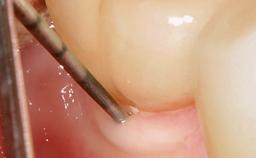

Resective Surgical Treatment of Peri-Implantitis Including Implantoplasty

In this case, Myroslav Solonko, Ignacio Sanz Sánchez and Mariano Sanz present a treatment that aims to eliminate exposed implant threads by modifying the implant surface, converting a moderately-rough surface into a smooth surface.